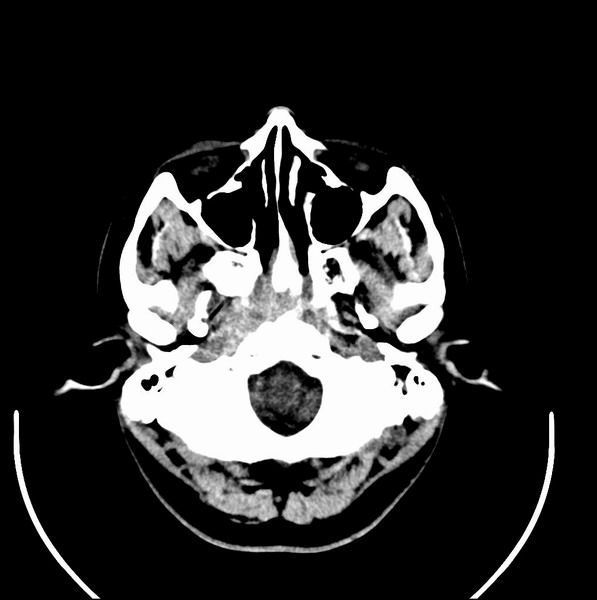

扫描示鼻咽腔不对称,中度狭窄,右侧咽隐窝消失,局部软组织肿块,鼻咽右侧壁增厚形成肿块,突入鼻咽腔,肿块平扫呈等密度,肿块向深部侵润,右侧翼内外肌受侵,右侧咽旁间隙变窄;向后生长,头长肌界线欠清,向后上生长侵犯同侧颈动脉鞘区。双侧海绵窦增宽,内见软组织影与鼻咽部肿块相连。考虑鼻咽癌。鼻咽癌主要是放射治疗,且效果较好;到当地有治疗设备较大医院治疗即可。

这个病例有点特殊,和常见的鼻咽癌不太一样,以向颅内侵犯为主,骨质破坏区小。鼻咽癌首先要考虑,有没有其他可能?本人不会看mr片,期待有人能讲解,期待病理。

鼻咽部新生物(纤维血管瘤?鼻咽癌?)侵犯右侧中颅窝底及右侧海绵窦;建议必要时活检定性。